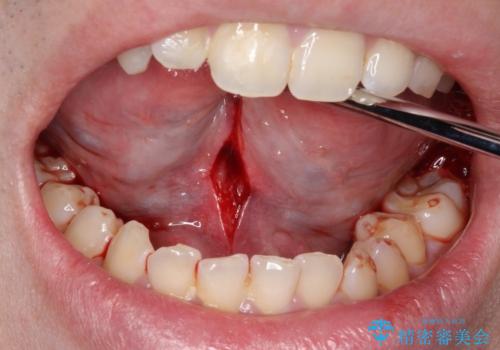

- 以前から舌小帯が短いと指摘されていた。日常生活の中で、少し話しにくいと感じるとのことで来院されました。

舌小帯が短く、小帯が下の前歯に引っ掛かり痛みが出るなど、日常生活に支障をきたしているため、舌小帯形成術を行うことにしました。

手術は局所麻酔下で行われ、舌小帯を切開し、縫合します。